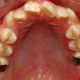

Los investigadores descubrieron que un 73% de los niños tenían caries, estableciendo bajo este parámetro una conexión entre salud oral y bajo rendimiento escolar, encontraron que la mayoría de niños que se quejaron de dolores en los dientes presentaban mayores probabilidades de tener calificaciones más bajas o por debajo de la media, en comparación con los niños sin dolor bucodental, principalmente porque los niños que se quejan de este tipo de problemas suelen faltar más a la escuela; una media de unos seis días al año, a diferencia de los compañeros que están sanos.